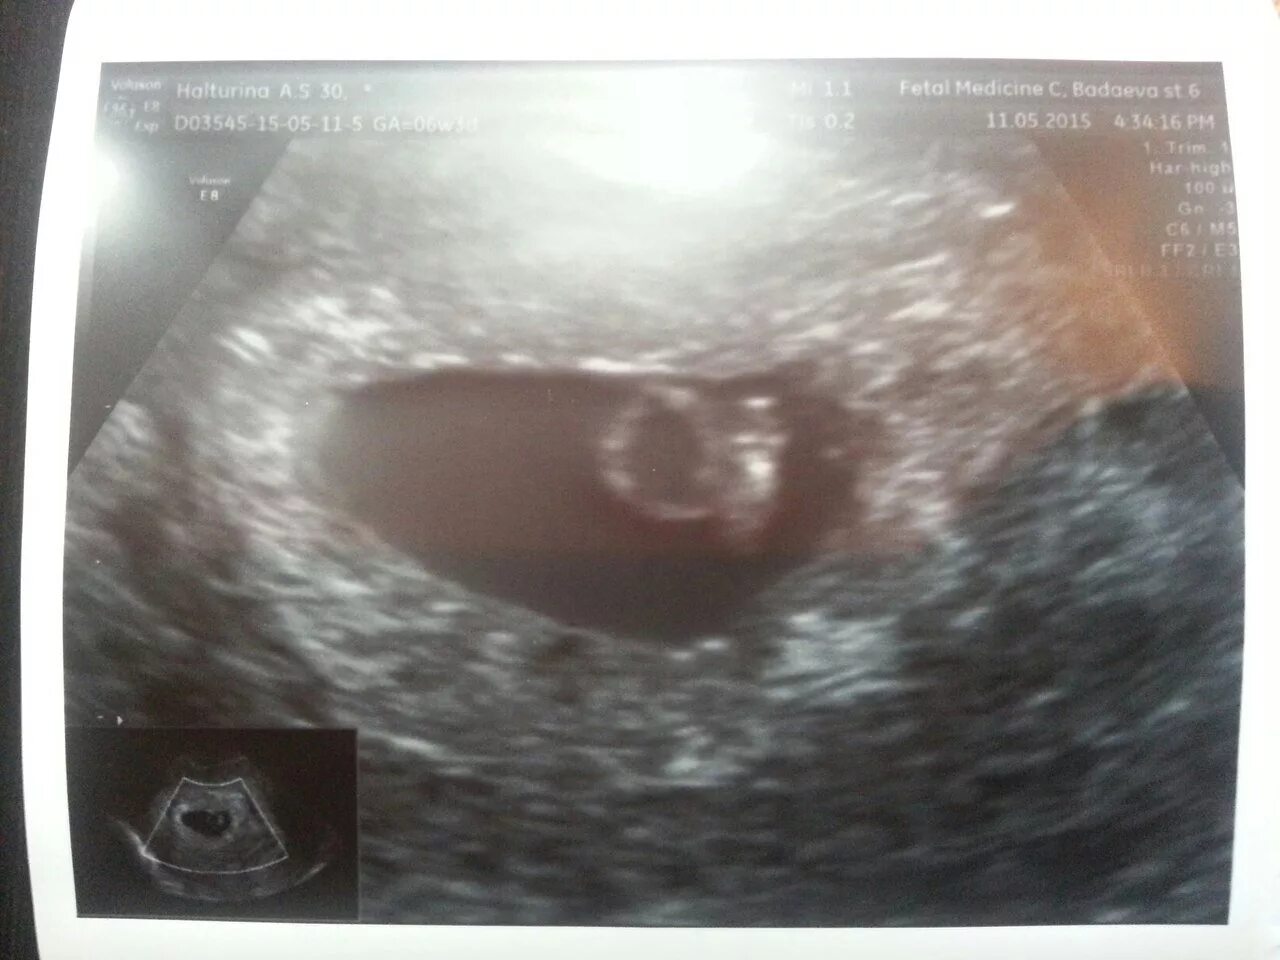

3 нед 4 дня